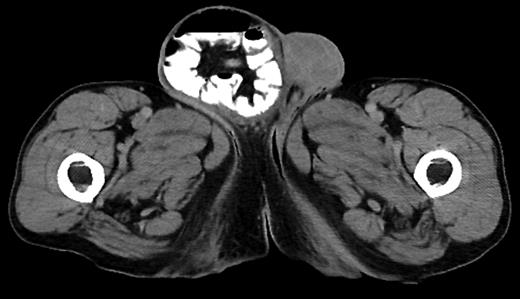

This case presented a specific scenario in which a patient with an umbilical hernia, right inguinal hernia and a duodenal tumor presented for surgery. In this case, removal of the tumor was immediately necessary, while the other two procedures could have been delayed for another time. In an effort to spare this patient from the risks of multiple procedures, it was decided that combining the procedures may result in a better outcome for the patient. The duodenal tumor was removed using standard laparoscopic technique; however, the specimen was removed through the opening created for the open right inguinal hernia repair.

The usefulness of such combination procedures will vary greatly from patient to patient. We hope that as such procedures are reported more often they will inspire other surgeons to attempt more creative combinations when opportunity presents, maximizing the advantages of minimally invasive methodology.